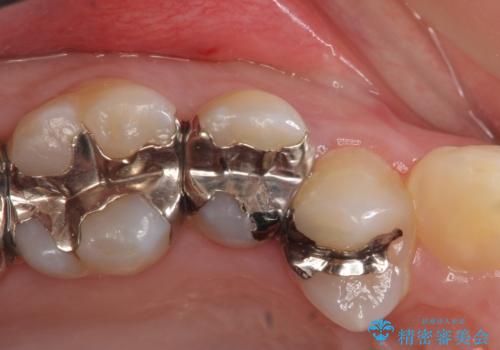

- 頬側から見たとき右上5番目の銀歯が気になるので、オールセラミッククラウンによる補綴を行った症例です。